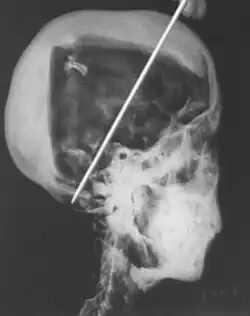

1968 X-rays

In 1968 R. G. Harrison, a professor of anatomy, used a portable X-ray machine to re-examine the mummy of Tutankhamun. Harrison quickly discovered that Carter had dismembered the mummy, something that is not mentioned in his publication but visible in photographs of the unwrapping. The mummy, surrounded by cotton wool and secured by modern bandages, had deteriorated since last photographed by Carter's team in 1926. The beaded skull-cap had disappeared, as had most of the skin on the head. The eyes appeared to be wide open as the eyelids had been destroyed, and the ears were broken off. The ribs had been sawn off and the front of the king's chest, including sternum and clavicles, had been removed. Stray beads from the large beaded collar were seen scattered in the torso on the X-rays. The limbs had been moved and further disarticulated, with the left hand and thumb of the right hand found in the sand under the body, and some of the digits on the hands and feet missing.[80][58][81] Although not mentioned by Harrison, the king's penis was also missing.[81] The additional damage to the mummy and the removal of the skullcap and collar likely occurred during the Second World War,[58] and components suggested to be from the collar have since appeared on the antiquities market.[82]

The X-rays revealed two levels of resin inside the skull. One was introduced when the body was lying on its back, pooling at the back of the head; the other when the head was tilted far back, settling at the top of the skull. Also present in the skull cavity were small bone fragments which Harrison initially believed to be the result of the embalming process. The fact that skull fragments were discovered led many to assume the king was murdered by a blow to the head, but the X-ray could not support or discredit this theory. His age at death was again estimated to be around 18, with a projected height in life of 168.9 centimetres (5 ft 6.5 in).[80] Serological analysis undertaken by the same team determined that Tutankhamun and the KV55 mummy had the same blood group, further indicating a familial relationship.[83]

The initial examination of the mummy reported the body showed "no traces of the cause or causes of the young king's death".[104] Bone fragments seen inside the skull in the 1960s X-rays led Harrison to propose that Tutankhamun died from a blow to the head. This has led to "endless speculation as to whether (or how) the king was brutally attacked or murdered",[92] with Tutankhamun's vizier Ay considered the most likely culprit as he stood to gain the most from the young king's early death and ultimately succeeded him as pharaoh.[105][102] A violent murder is ruled out because it is now known that they are a result of the mummy's modern unwrapping as the fragments are loose inside the skull[106] and there is no evidence of bone thinning or calcified membranes indicative of a fatal blow to the head.[107] Death as a result of a brain tumor[108][109] was also not supported by anatomical studies.[110]